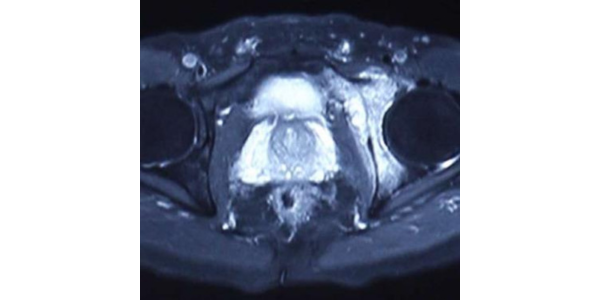

A male patient of 50 years old hailing from Mumbai, Maharashtra, presenting with complaints of pain in left groin. Imaging followed by Biopsy concluded Grade II Chondrosarcoma.

Dr. Manish Agarwal, India’s leading Onco Orthopedic surgeon in Mumbai, Maharashtra being a pioneer in using treated tumor bone/ECRT as a method of reconstruction aided surgeries studied medical history, imaging and histopathology reports. It was decided to proceed with ECRT line of treatment. Salvage of acetabulum with ECRT is more of challenging procedure due to complex anatomy of hip, limitation on access due to vital organs in pelvis and particularly due to functionality of load bearing joint. Hence Dr. Manish Agarwal decided to use patient specific cutting guide and patient specific anterior and posterior plate to fix radiated bone fragment back to the position to give maximum functional benefit to the patient. 3D Incredible team discussed with Dr. Agarwal, the designing and entire manufacturing process. Read more